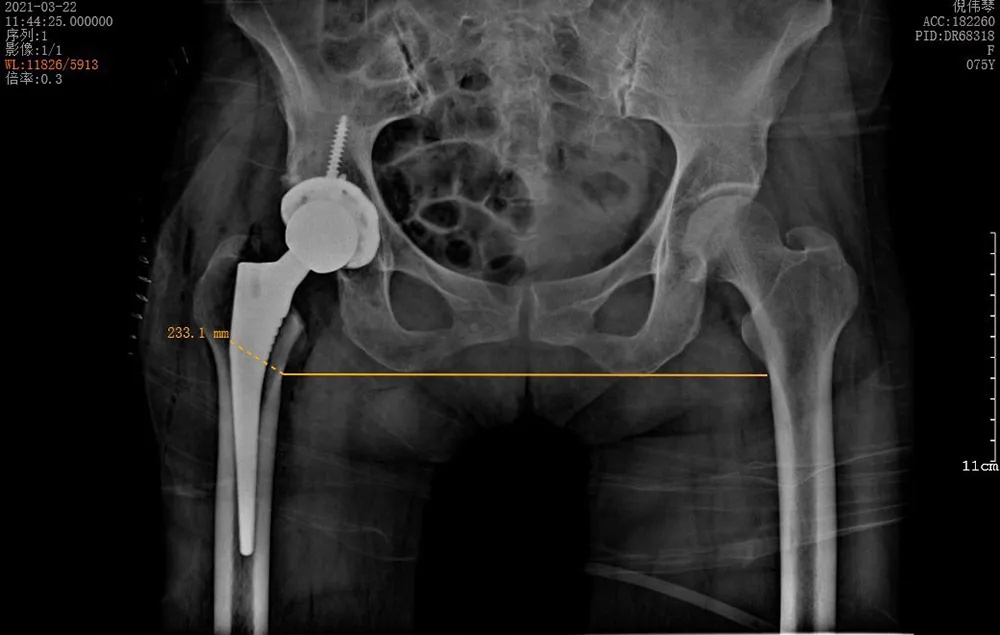

3月22日,在將倪阿姨的身體調(diào)整到最佳狀態(tài)并完善所有術(shù)前準(zhǔn)備之后,羅軍團(tuán)隊(duì)為她進(jìn)行了手術(shù)。術(shù)中發(fā)現(xiàn)其股骨頭完全壞死,而且患者的骨質(zhì)疏松嚴(yán)重,所有操作必須十分小心,幸好有精準(zhǔn)的AI-HIP術(shù)前規(guī)劃,手術(shù)歷時(shí)1個(gè)小時(shí)就成功完成,全程出血不到50ml。

↑術(shù)后雙下肢完全等長